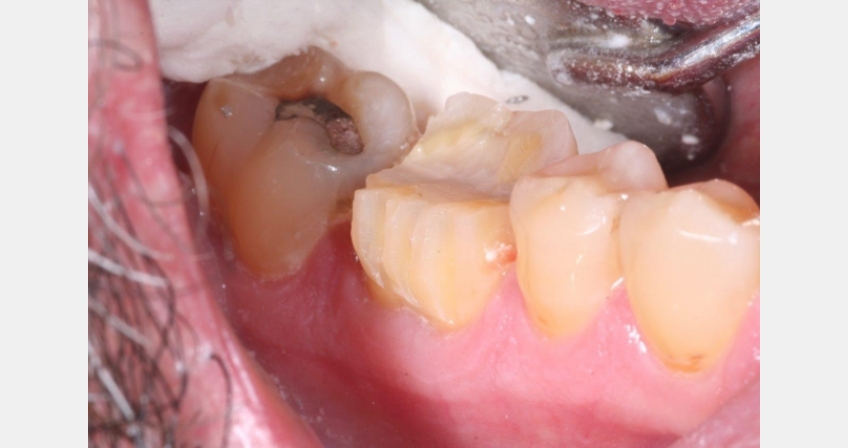

- I will then take the same bur on the facial and lingual and do depth cuts in two planes: in the incisal 1/3 and then to an approximate area of the margin along the gingival height. This bur is 1.0 mm in diameter, so adjust as needed for material choice. Be sure to account for the facial/lingual area where you need added thickness for the functional cuspal area.

- Place the bur back in the depth cuts and pull/push again to quickly remove the segments of tooth remaining between the depth cuts. Cutting these segments away at this stage is more efficient than milling the tooth back and forth. Once the enamel is reduced, you can easily smooth and refine the margins.

- Carry the bur carefully between the interproximal areas to break contact and follow the gingival contours and/or restorative material.